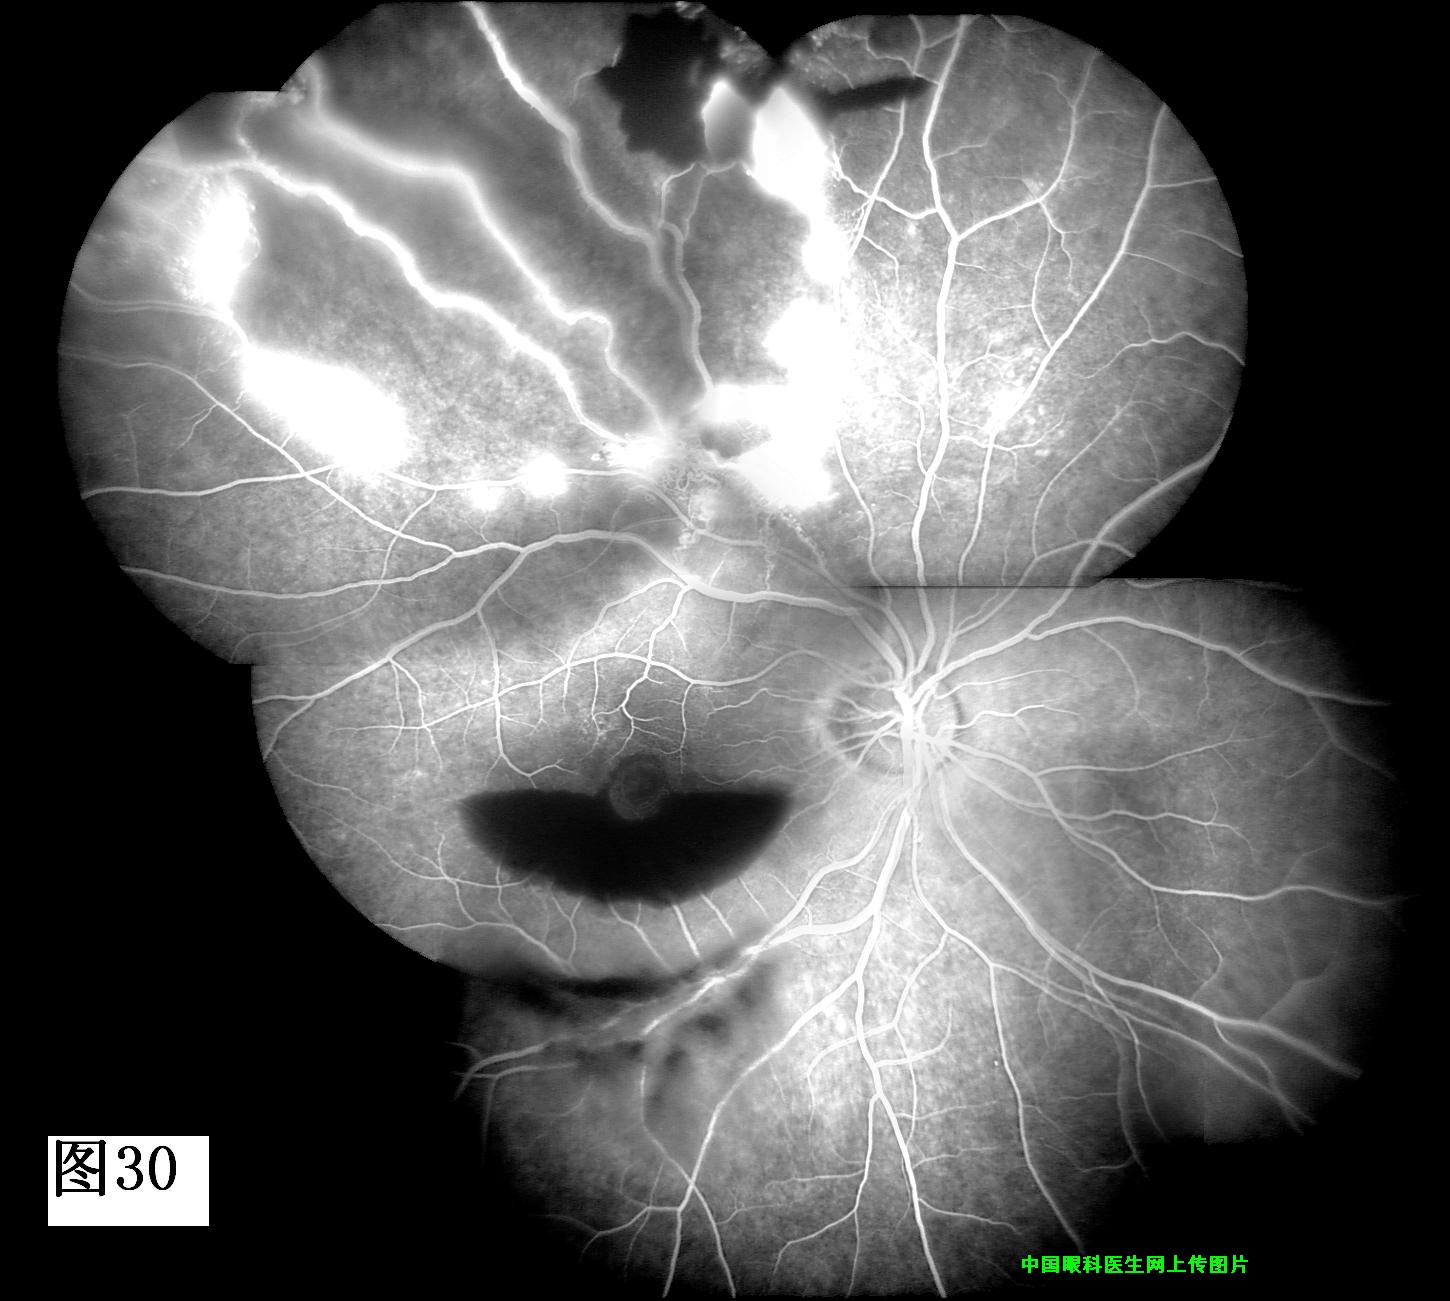

29 30 31 32